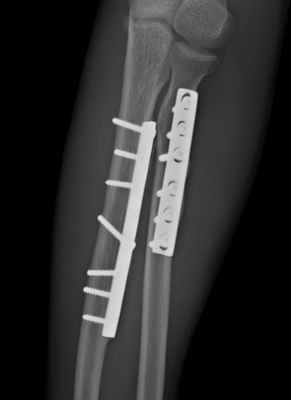

Остеосинтез стержнями часто не обеспечивает стабильной фиксации, а введение прямого стержня в лучевую кость приводит к выравниванию физиологической кривизны лучевой кости, что ведет к нарушению ротационных движений.

При переломах диафиза и метафиза обеих костей или изолированных переломах лучевой и локтевой костей остеосинтез производят прямыми узкими, желобоватыми пластинами.

Принципы экстракортикального остеосинтеза костей предплечья.

Остеосинтез при переломах дистального отдела лучевой кости производят редко, как правило, при неудаче консервативного лечения. Для остеосинтеза применяют малую Т-образную пластину (Рис. 140).

Первый винт вводят через продолговатое отверстие в проксимальный отломок, тем самым создавая опору для дистального фрагмента. Сам отломок фиксируют компрессионным спонгиозным винтом через отверстие пластины. Рану ушивают с тщательным восстановлением квадратного пронатора. Движения в лучезапястном суставе разрешают через 3–5 дней.

Остеосинтез лучевой кости в дистальном отделе